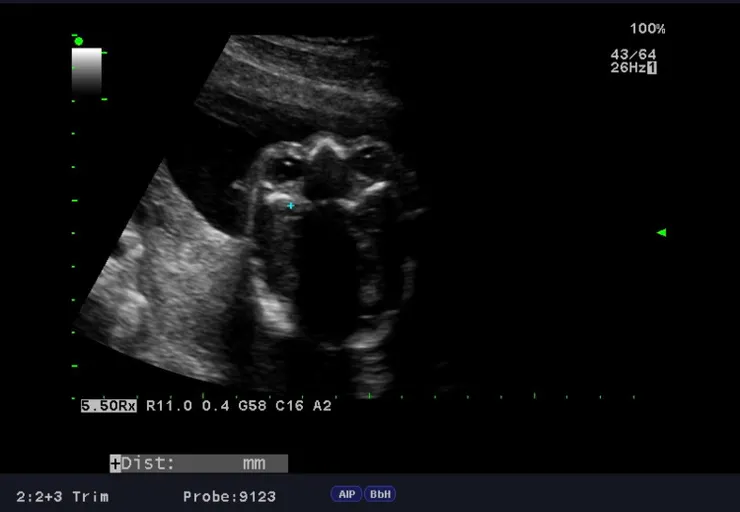

接著台兒的林薇醫師接手,又重複地進行第二輪掃描,細心的林醫師對我講解著螢幕上顯示的各個器官與狀態,當她照到寶寶的心臟時,特別仔細地檢查各個心室心房的大小以及血流的方向。

我看著螢幕上顯示的心臟,猶如教科書上繪製的兩個心房與兩個心室,搭配著血液流入與流出不同方向顯示不同的顏色,這是我第一回看到真實人類的心臟與血流,而且這顆心臟還是屬於一個正在長大的胎兒!我想到懷孕六週時,第一次聽到這顆心臟強而有力跳動的聲音,生命的起源正來自於此,讓人又是一股感動。